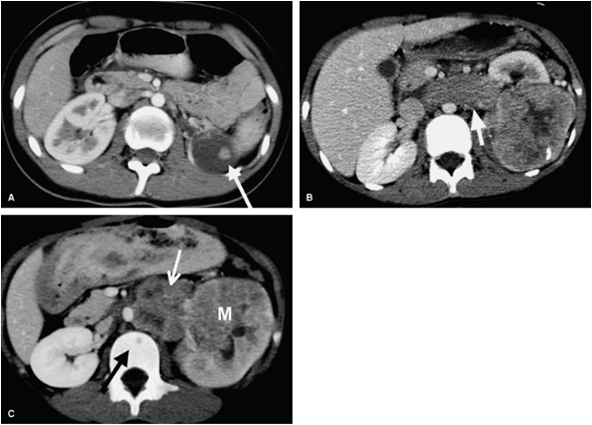

Look to the coming image below

Lymphoma

Multiple parenchymal renal masses usually have negative mass effect on the edge of kidney

Look at the spleen for further lesions and for retroperitoneal area for bulky lymph nodes

Usually seen in immuno compromised patient as in AID'S

![]() |

| Contrast enhanced CT image at the level of renal hila shows bilateral, smoothly enlarged kidneys showing a striated nephrogram. No focal lesions were identified |

Golden rule

¨Evidence of bilateral kidney diffuse enlargement with scanty area of secretory system enhancement suggest renal lymphoma

¨Lymphoma appears hypo echoic by ultrasound as a cystic lesion .In case of renal lymphoma , we can found diffuse hypo echogenecity of kidney